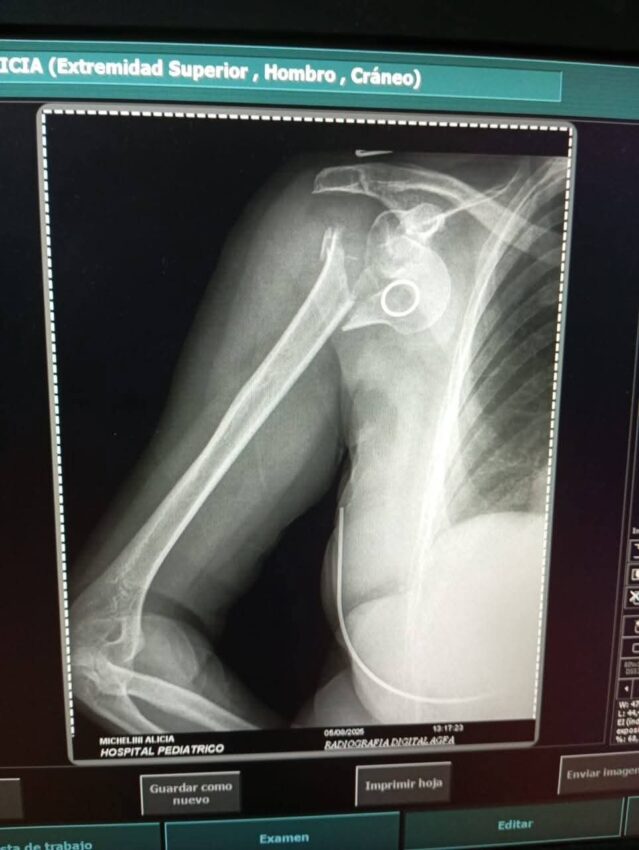

El hecho ocurrió sobre la calle José Hernández al 400, cuando los delincuentes la abordaron para robarle un portafolio que contenía una netbook color gris y un teléfono celular Samsung modelo A20 con funda azul eléctrico. Producto de la agresión, Michelini sufrió una grave lesión en el hombro que requerirá intervención quirúrgica.

En sus redes sociales, la doctora Michelini expresó: “Por lo pronto me queda afrontar una cirugía ortopédica donde me colocarán una prótesis en el hombro, dado que las lesiones son graves y la recuperación delicada. Confío que, con Dios mediante, todo saldrá bien. Aquellos que me conocen saben que no me van a faltar fuerzas y garras para hacer la rehabilitación como corresponde.”